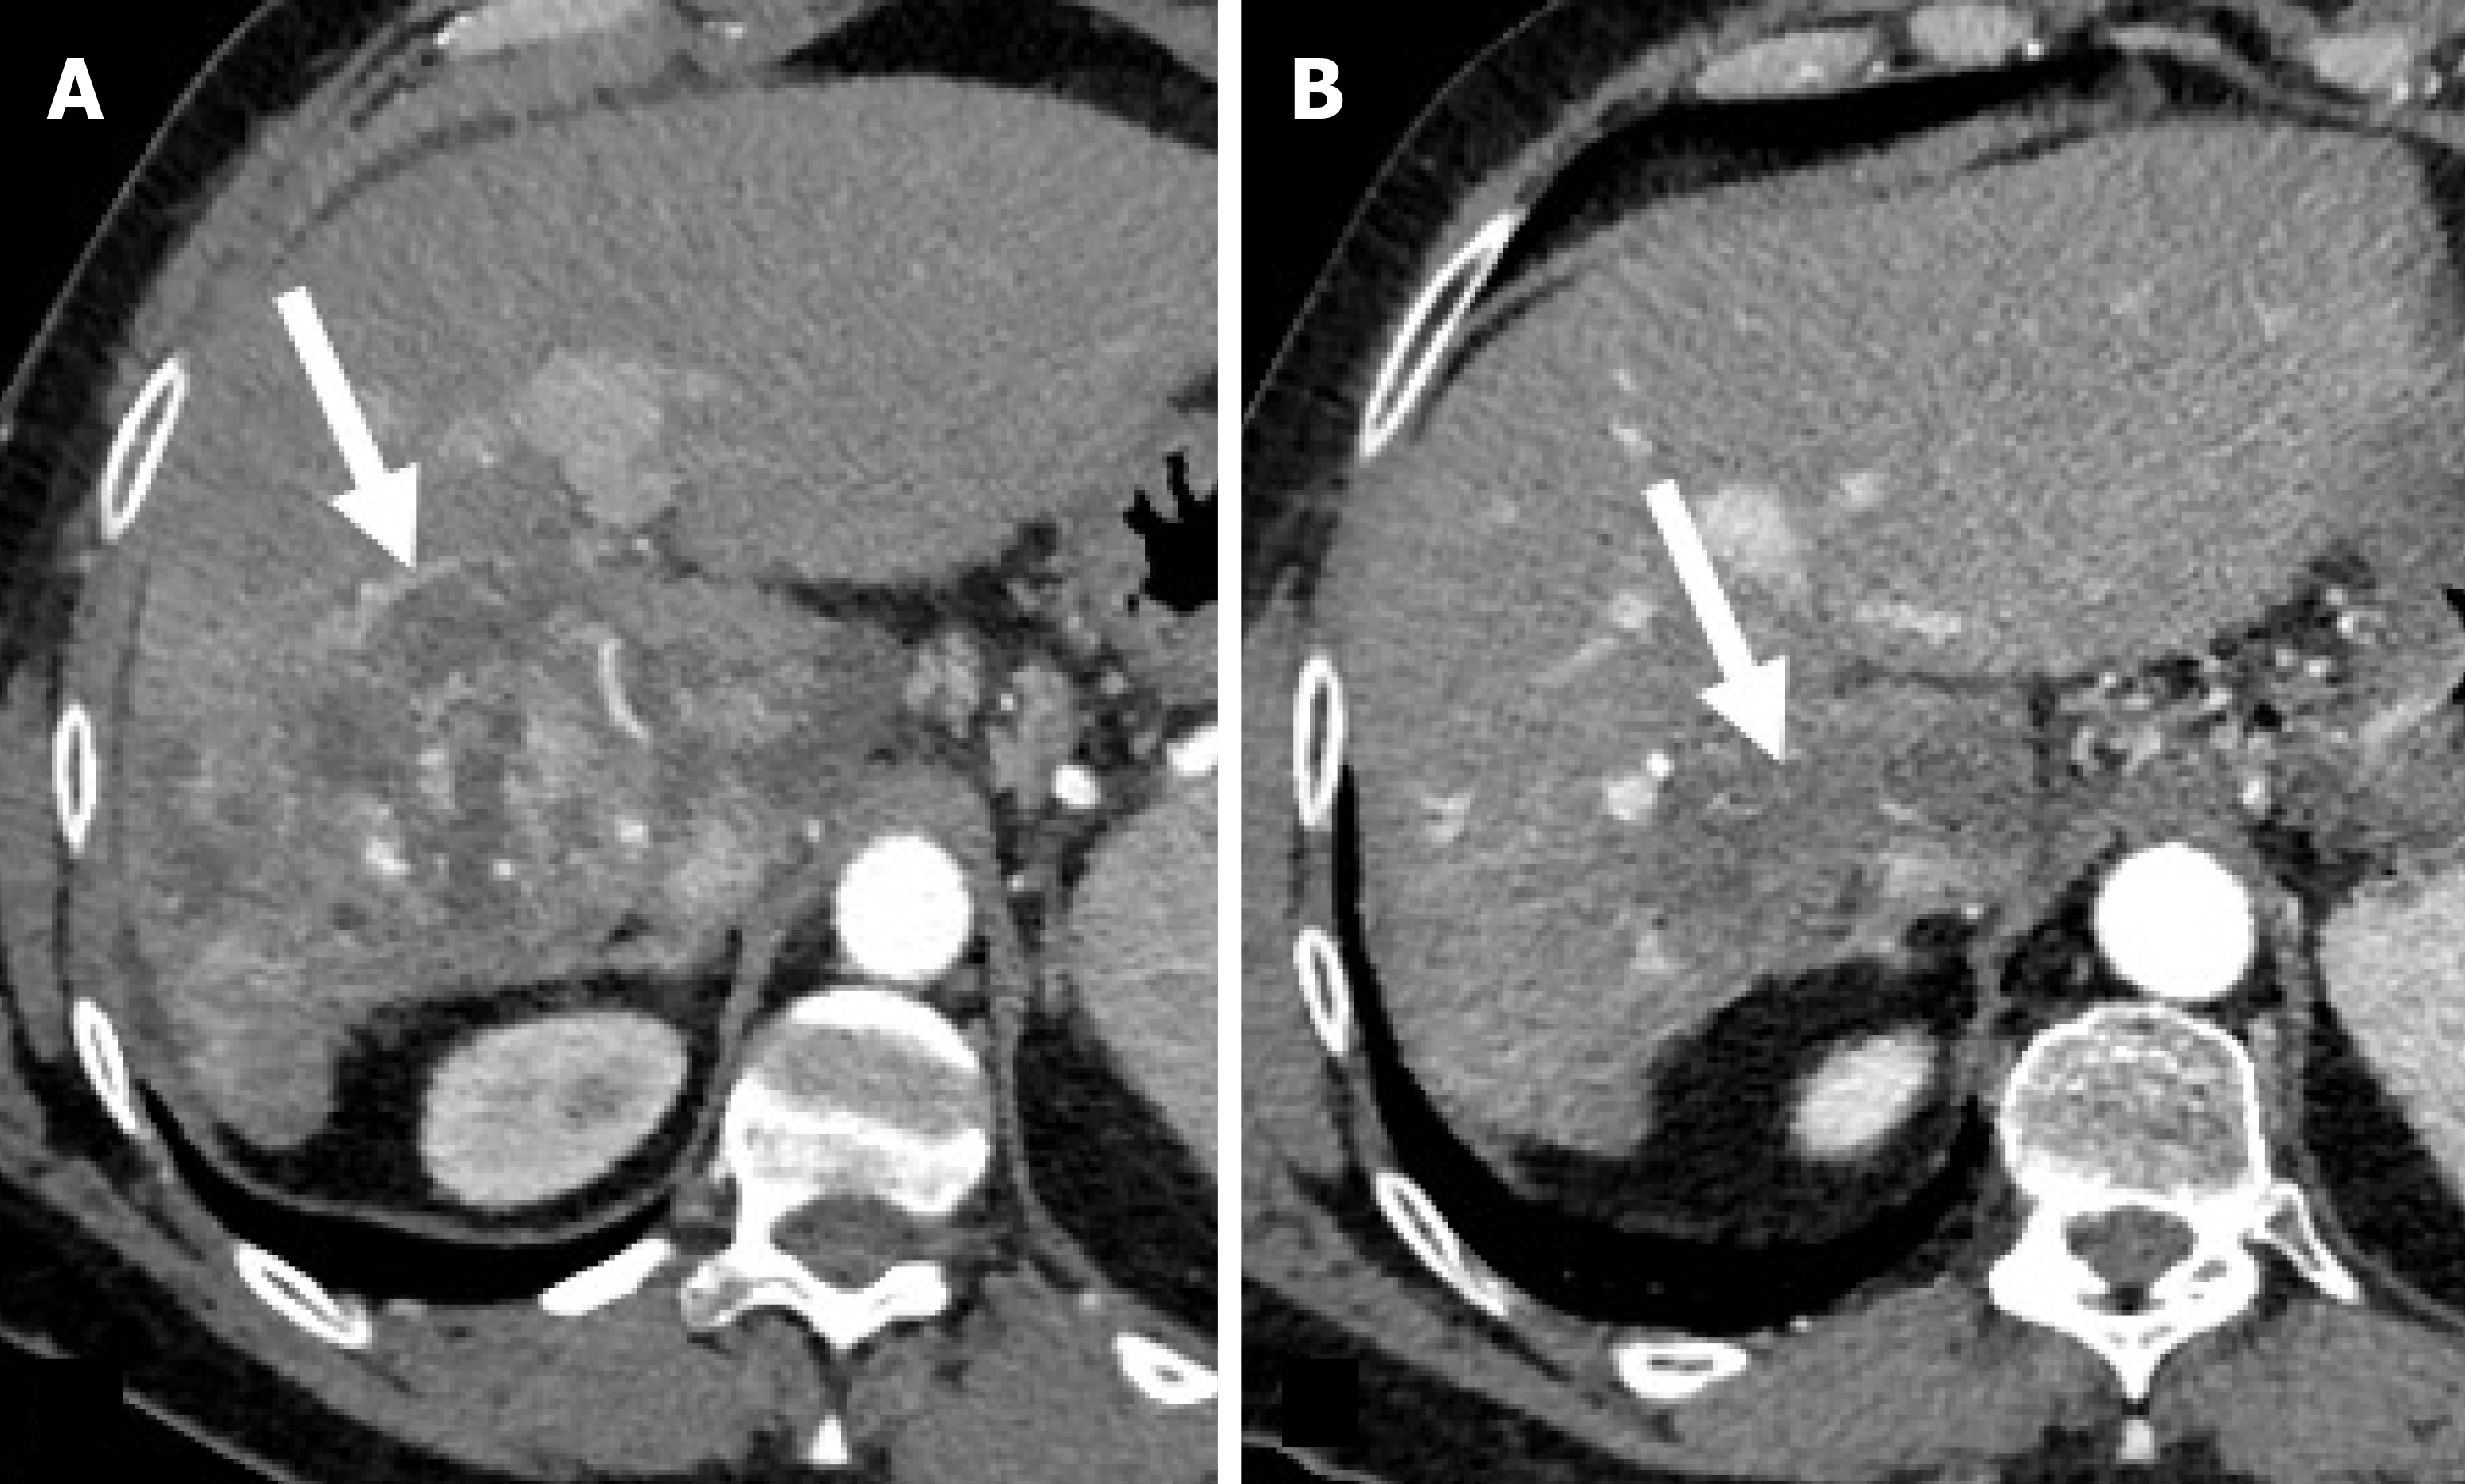

Figure 2 Residual hepatocellular carcinoma after trans-arterial chemoembolization in a 72-year-old man with hepatitis C virus-related hepatic cirrhosis.

A: On unenhanced computed tomography obtained one month after trans-arterial chemoembolization the residual tumor (dotted arrow) shows no Lipiodol retention and the necrotic tumor (arrow) shows homogeneous Lipiodol retention; B: On hepatic arterial phase the residual tumor shows enhancement and the necrotic tumor shows no enhancement; C: On delayed phase the residual tumor shows wash-out.